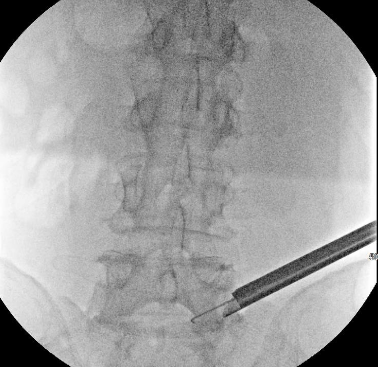

One of the most exciting advancements in spine care is endoscopic spine surgery. With smaller incisions, less pain, and faster recovery times, this technique is revolutionizing how patients are treated. Despite its incredible benefits, endoscopic spine surgery remains a specialized field:

Explore how robotics, navigation systems, and endoscopic tools enhance precision and efficiency in surgery. These innovations are making procedures more accessible and reducing the risk of complications.

- Cutting-Edge Technology